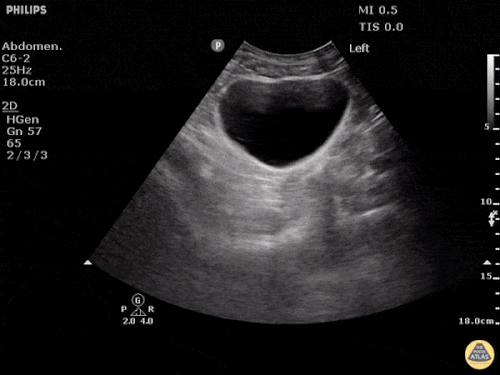

FAST: Morrison Alanı ve Normal FAST Görüntüleri

Normal FAST – Sol Üst Kadran (LUQ)

Değerlendirmede amaç hipoekoik veya anekoik sıvı saptamaktır. Hipotansif travma hastasında peritoneal boşlukta görülen hipoekoik sıvı genellikle kan olarak kabul edilir.